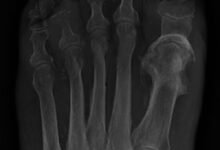

X-rays

X-rays reveal bone damage, but they are only effective if the injury has been several weeks old.

If the injury was recent, more detailed imaging tests are needed.